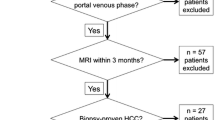

Forty patients with hepatocellular carcinomas were investigated with abdominal dual-energy CT. In each patient unenhanced and contrast-enhanced imaging with arterial und portovenous delay were performed. Hypervascular lesions were documented on arterial phase 80-kVp images, 140-kVp images, and the averaged arterial images by two radiologists. Subjective image quality (5-point scale, from 5 [excellent] to 1 [not interpretable]) was rated on all images.

Between April and August 2009, 40 consecutive patients (29 men, 11 women; mean age 64 years±10 years) underwent dual-energy CT (DECT) for evaluation of the liver for hypervascular lesions. This study was approved by our institutional review board and all patients provided written informed consent before participation.

The mean attenuation values of 80 kVp- and 140 kVp images for hypervascular hepatic lesions in the arterial phase were 119.3 ± 33.5 HU and 77.5 ± 16.6 HU, respectively. On averaged images attenuation was 91.7 ± 21.3 HU. This was significantly different from 80-kVp- and 140-kVp images (p <0.001 for both comparisons, Fig. 1). All other anatomical regions (liver, fat, aorta, muscle, air) differed significantly when the three datasets were compared (Table 1).

The number of detected lesions on 80-kVp, 140-kVp and averaged images was 3.4 ± 1.3, 1.4 ± 1.1, and 2.6 ± 1.2, respectively. These differences were significant (Table 2).

Liver delineation

In 25 examinations the liver underwent complete imaging with the 26-cm field-of-view detector; in 15 examinations liver coverage was incomplete. Potential incomplete coverage of liver parenchyma with the 26-cm field-of-view detector was rated as 0.58 ± 0.59 (range, 0–2; SD, 0.59) on the five-point scale.